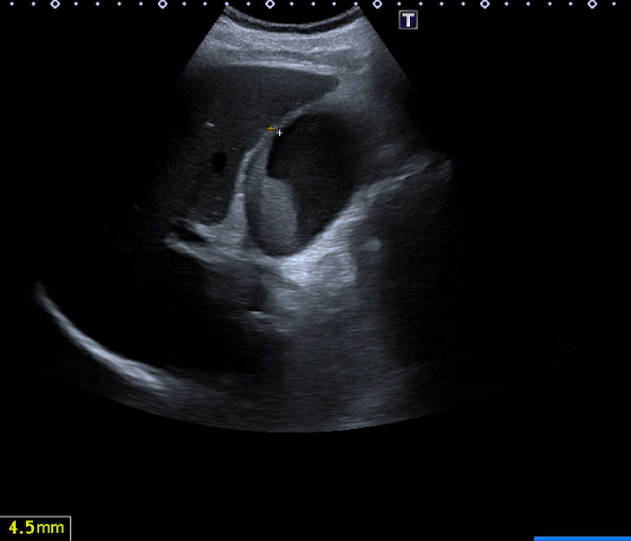

Se realiza una exploración abdominal, donde se objetiva distensión de la vesícula biliar, con un diámetro longitudinal de 10 cm, y engrosamiento de la pared de 4 mm (figura 1), abundante barro biliar (figura 2) y la presencia de una litiasis en cuello vesicular (figura 3). Murphy ecográfico positivo. Doppler negativo, sin dilatación de la vía biliar (figura 4). No líquido perivesicular. Resto de rastreo sin alteraciones.